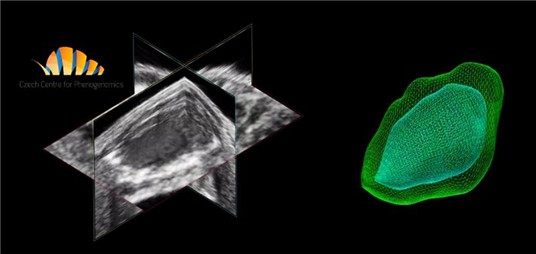

- 3D/4D Imaging for volumetric and dynamic visualization

Custom services Embryo Sonography (Fetal Sonography)

- Counting – Check plus accurate embryo counting via 3D scan.

- Assessment – Full evaluation: vitality, counting, 3D imaging, Doppler.

Fetal Echocardiography

For developmental studies, it is possible to monitor living mouse/rat embryos in uterus and follow the development of cardiac structures as well as changes in blood flow velocities in the heart and umbilical artery. An application of high-frequency probes with conventional 2D and pulse-wave Doppler imaging of the fetus can provide excellent information on the early development of cardiac structures.